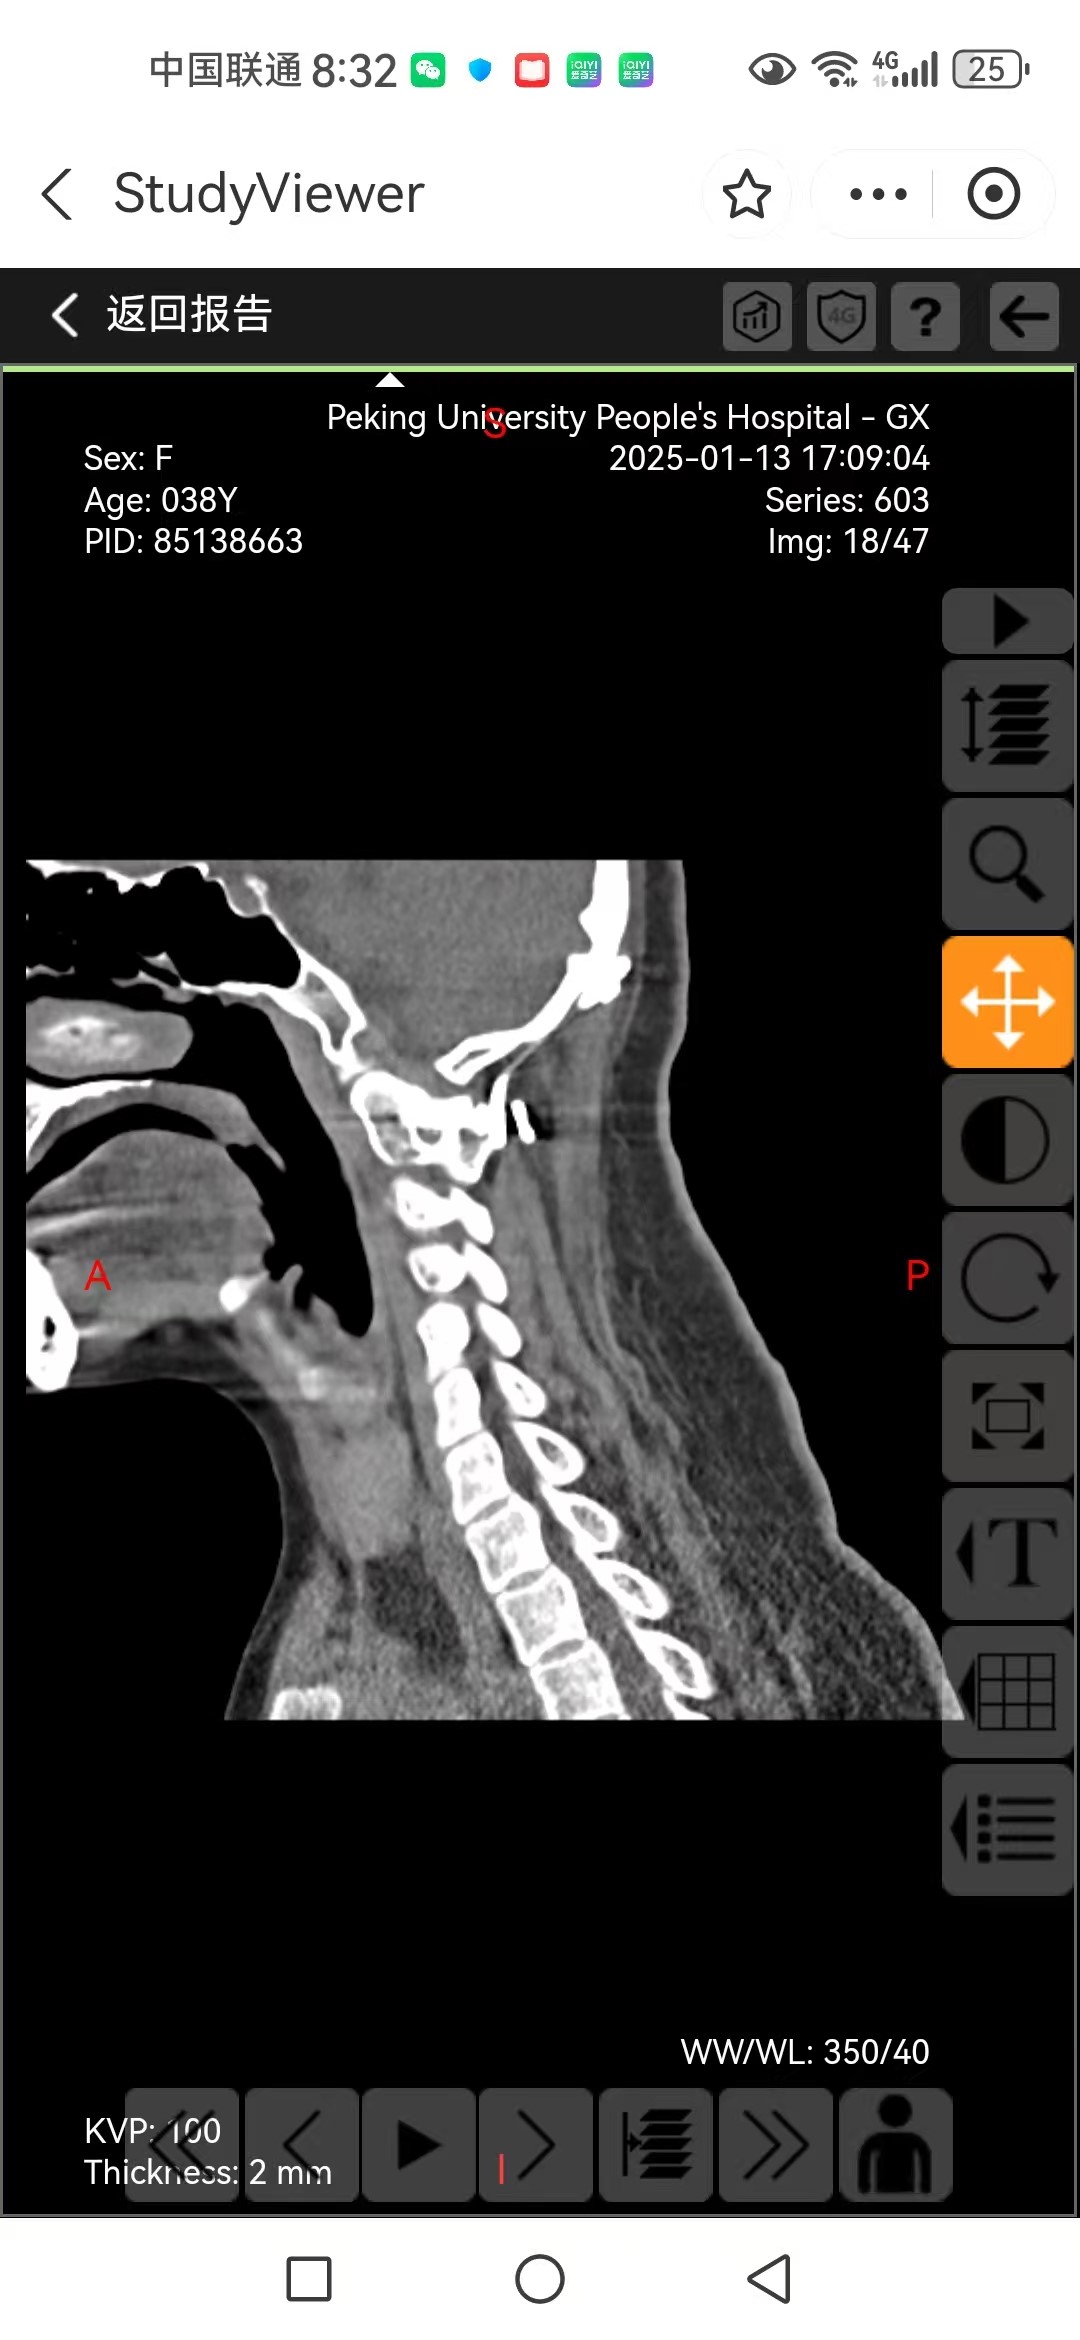

• 日期:2025.01.09

• 医院:人民医院

• 主刀:王超

• 术后影像: